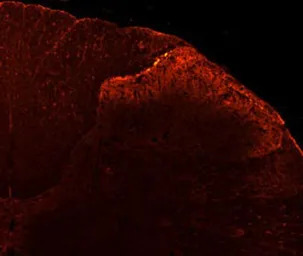

IHC analysis of rat dorsal horn tissue using GTX80798 VR1/ TRPV1 antibody.

Dilution : 1:100